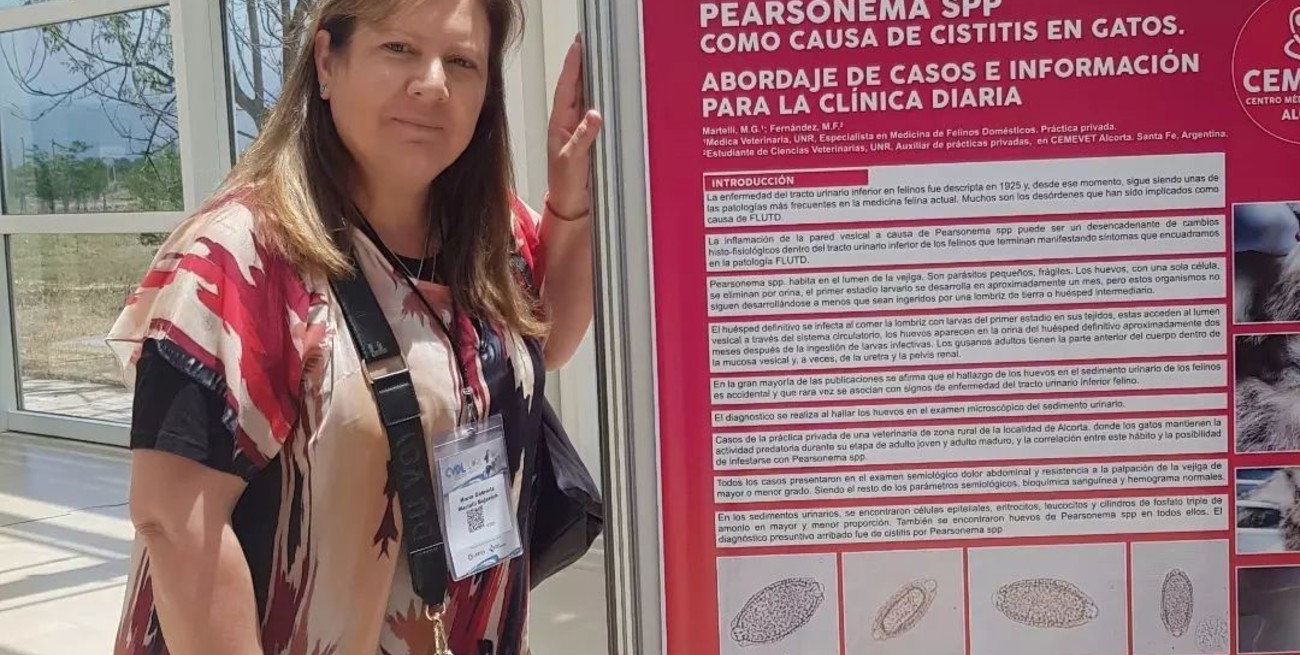

Maria Gabriela Martelli obtuvo el segundo puesto entre cientos de científicos argentinos por descubrir que los parásitos Pearsonema spp y Eucoleus, que habitan en el sur provincial, perjudican la salud de los gatos. Fue durante uno de los encuentros de veterinarios más importante de América Latina.

Allí, la médica veterinaria María Gabriela Martelli, de la localidad de Alcorta (departamento Constitución), presentó un trabajo de investigación científica y obtuvo el segundo puesto. La profesional, pudo aislar a un parásito que se encuentra en el sur provincial y que afecta la salud de los gatos principalmente.

En ese marco, Luna propuso a los cursantes de este diplomado presentar un trabajo final, bajo la modalidad de trabajo científico, que se vio plasmado en formato pósters. Ante médicos veterinarios de todo el país y países limítrofes, para poder exponer, Martelli tuvo que pasar por la evaluación de un comité científico que se focaliza en el desarrollo del tema, la forma de presentación, entre otras cosas.

En esa instancia resumió en 2 páginas, trabajos que generalmente son de no menos de 5 o 6. Una vez que fue aprobado, volvió a resumir el tema para plasmarlo en una gráfica con dimensiones y formatos académicos preestablecidos para exhibirlos los 3 días de duración del congreso.

Estos posters son una forma de comunicación de distintos trabajos de investigación, sintéticos, que permiten continuar aprendiendo a todos los que lo leen y también posibilita interactuar entre quienes se interesan en conocer más sobre el tema y quiénes los redactan.